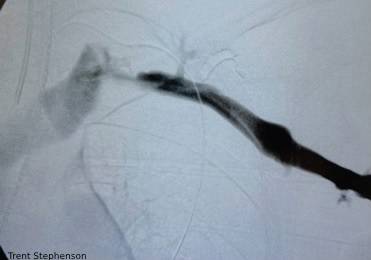

afterribremoved

By Jed Henson | on August 2, 2022 | 0 Comment